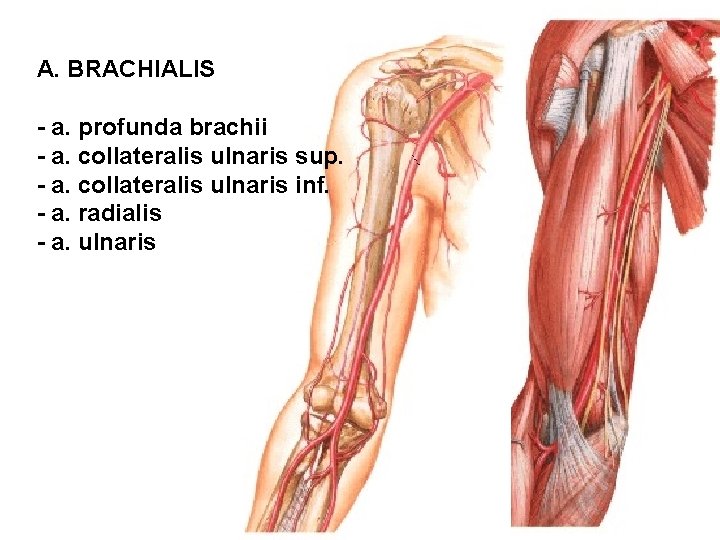

A. BRACHIALIS - a. profunda brachii - a. collateralis ulnaris sup. - a. collateralis ulnaris inf. - a. radialis - a. ulnaris